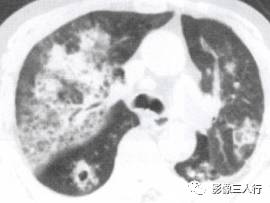

非典型肺炎的CT征象特点:分布不均匀、形态不同、大小不一的肺实变是本组 患者共同存在的基本CT表现。肺实变通常由于肺泡内充盈浆液性、渗出性或血性液 体、炎细胞或其他成分,导致肺实质弥漫性或局灶性密度增高。早期表现为边界不 清楚的0.5〜1.0cm的结节性高密度灶,随着病变的进展,融合成团块或斑片状阴 影,掩盖肺血管纹理。较大的实变影像内可见支气管分支的透亮影则为空气支气管征。见图9。